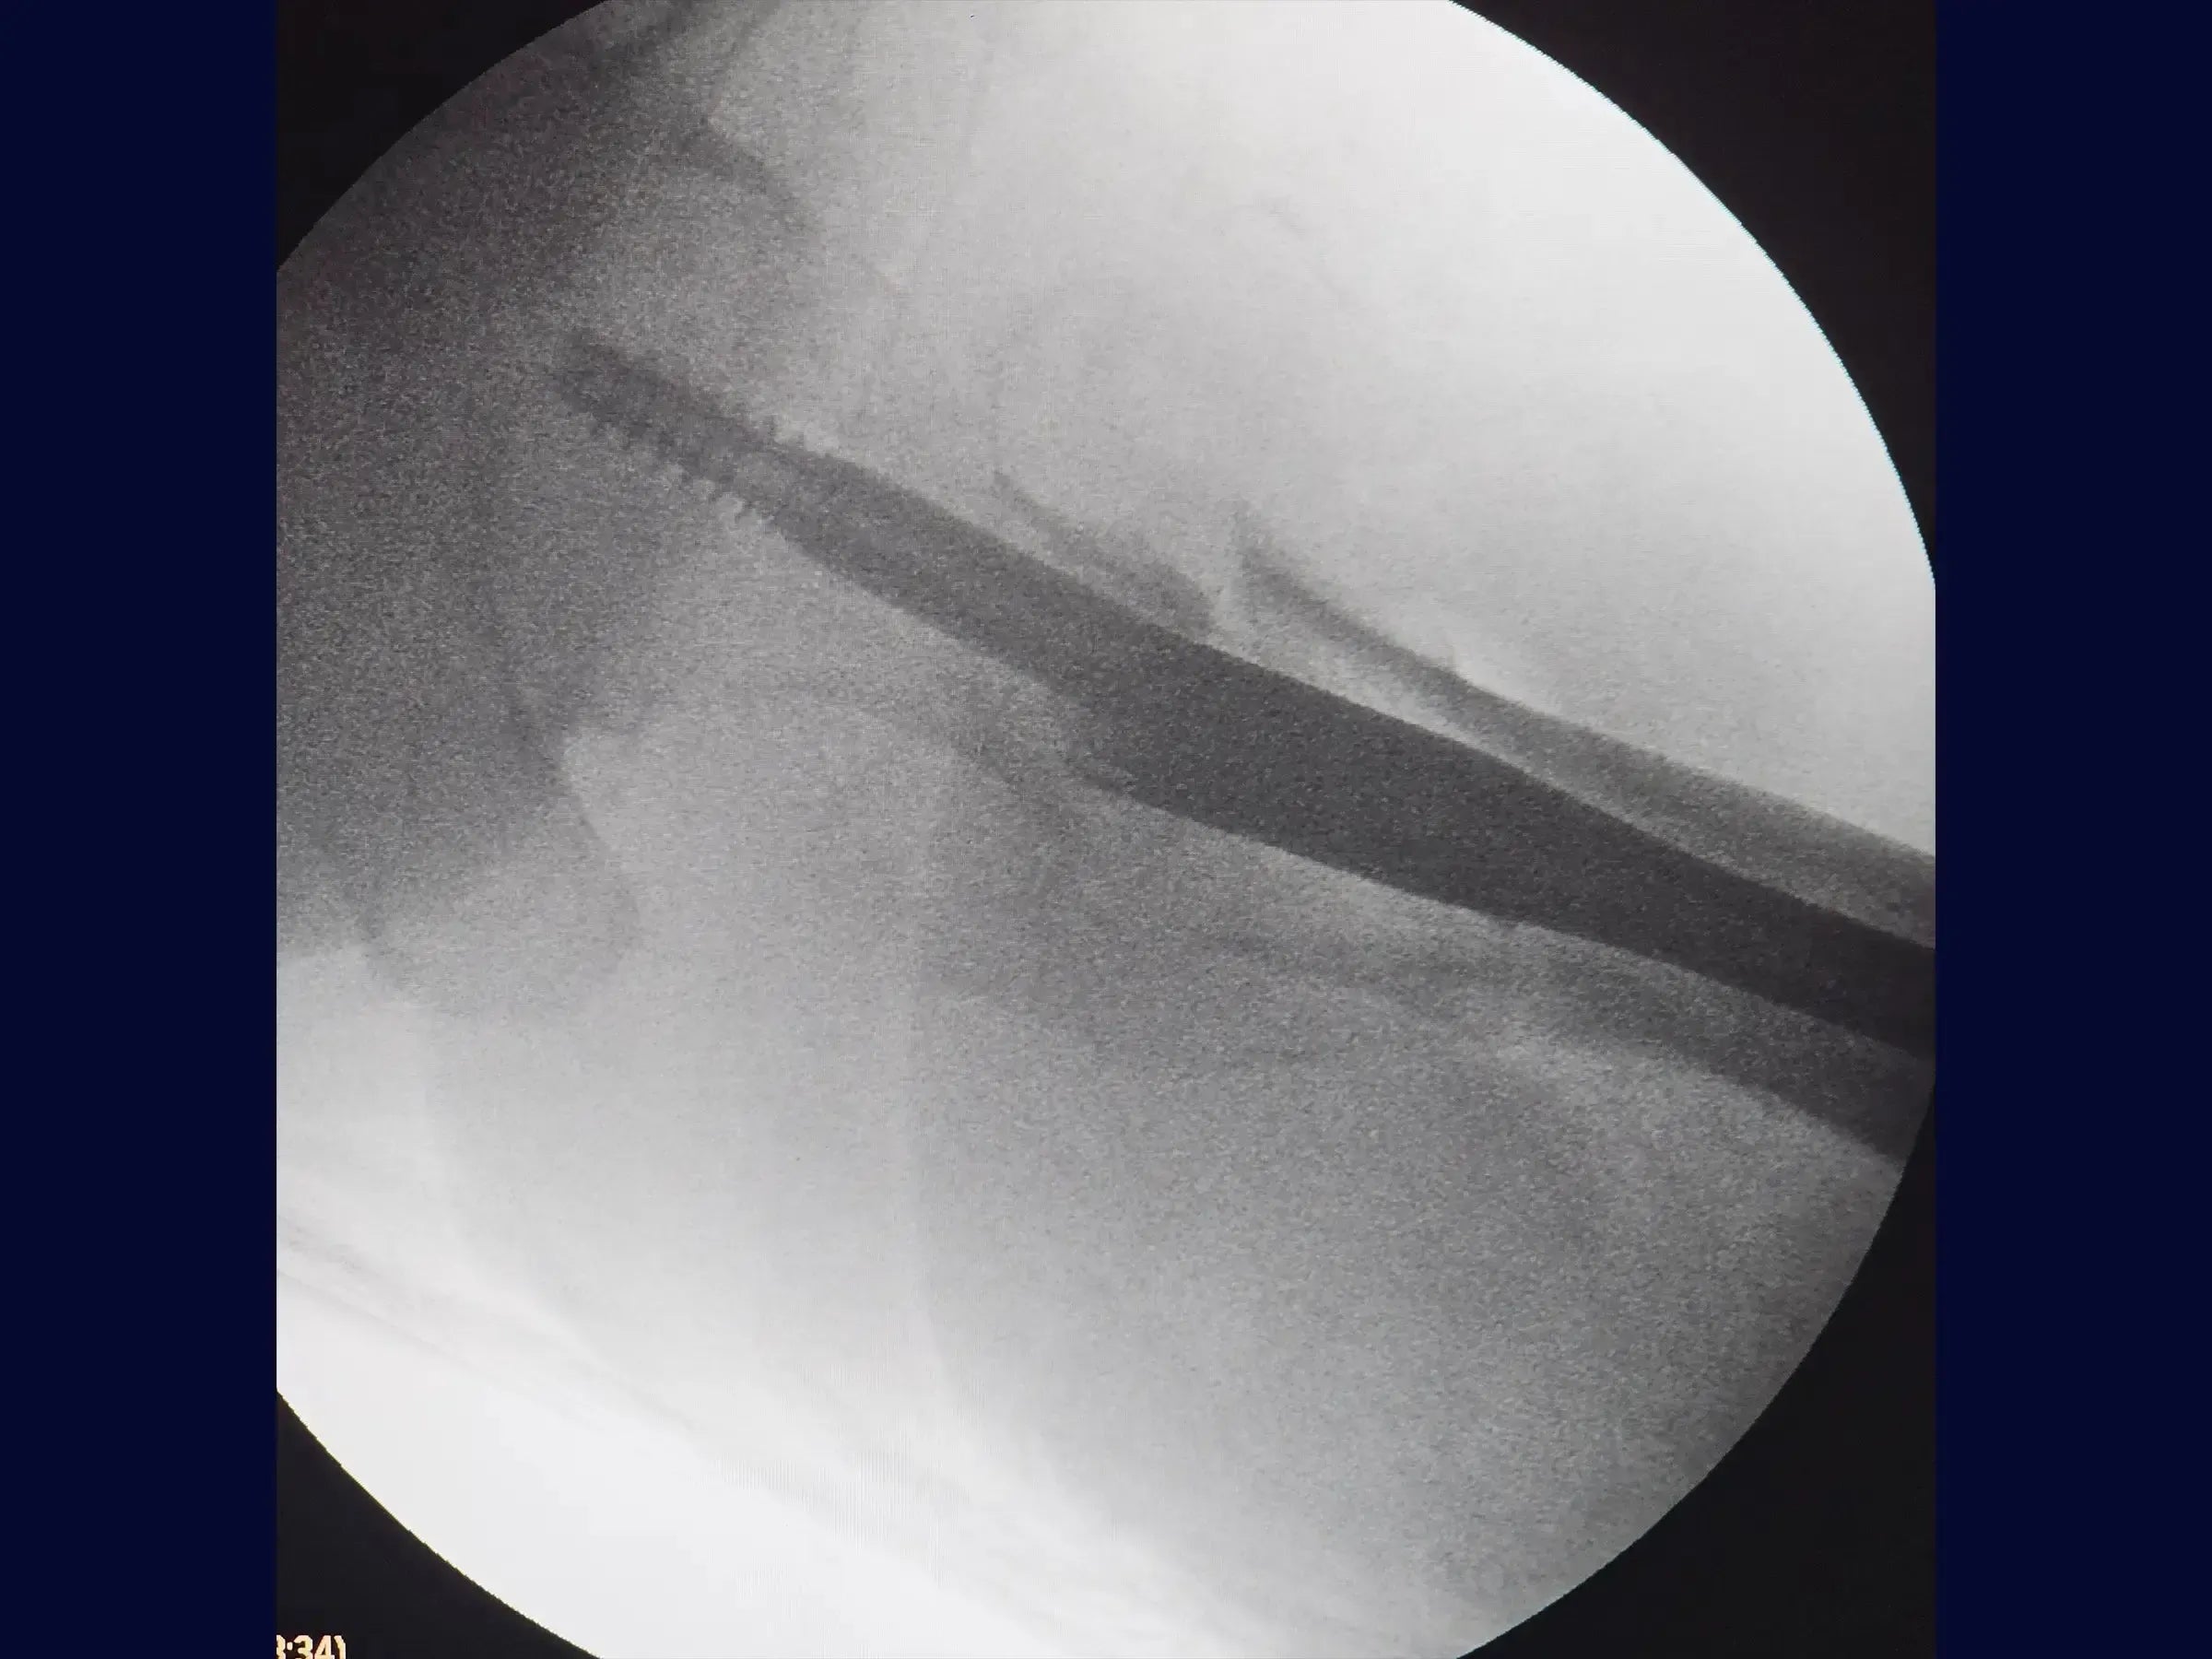

- Manejo de la inserción de guía y apertura del canal medular.

- Inserción precisa de la guía: protocolos para crear el portal de entrada alineado con la espina ilíaca anterosuperior, dar forma a la guía para lograr el mejor ángulo de ataque y realizar una comprobación radiológica para comprobar la centralización y la prevención de la oblicuidad.

- Apertura segura del canal medular: técnica para utilizar la guía/protector de tejidos blandos, dirigiéndolo medialmente para proteger la corteza lateral del fémur durante el escariado.